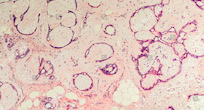

para el apoyo en el diagnóstico de cáncer

para el apoyo en el diagnóstico oncológico